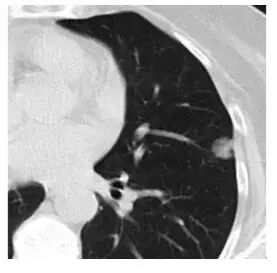

3. 隐球菌感染(「肺里面长蘑菇了」)

这个也像 GGO,还有一个小空洞

当逐渐长大进展,纯 GGO 的实性成分增加,成为「混合性GGO」。有时,还会出现分叶、毛刺、空泡,胸膜凹陷,血管密集等改变,这时多数已经是恶性了,为浸润性腺癌——可侵犯血管、肺内或全身转移。